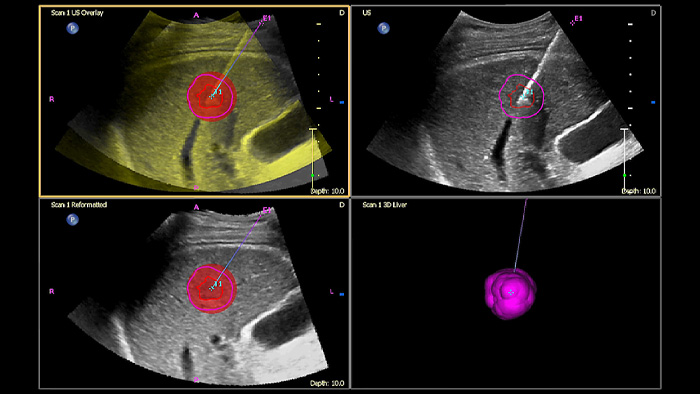

Prendi decisioni sicure anche in casi diagnostici complessi grazie alla fusione delle immagini e alla navigazione dell'ago di Philips. Il flusso di lavoro semplificato consente ai medici di ottenere una fusione rapida ed efficace di immagini TC/RM/PET con ecografia dal vivo, mentre la navigazione dell'ago aiuta a guidare la biopsia di lesioni di piccole dimensioni e di difficile accesso2.

Utilizzando il contorno del tumore, gli utenti possono pianificare e trattare le lesioni con uno strumento semiautomatico che aiuta a delineare un contorno 3D attorno a una struttura di interesse, migliorando potenzialmente la guida della procedura nei casi difficili in cui la lesione potrebbe non essere facilmente visualizzata.